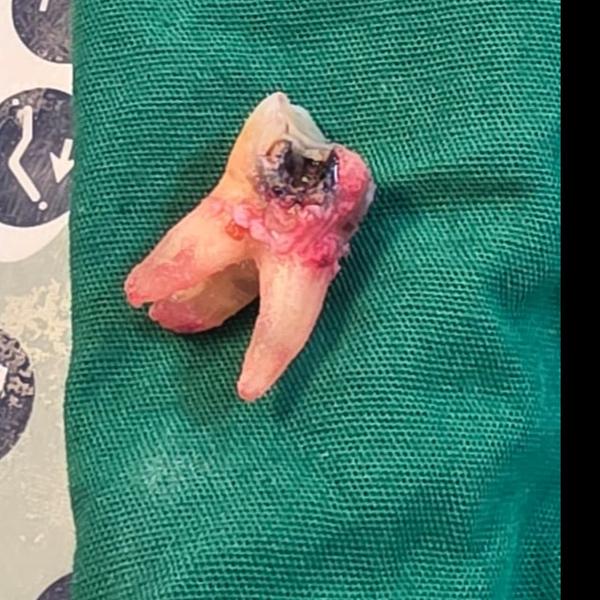

• Remove infected pulp inside the tooth

• Infected pulp is removed

• Avoids extraction